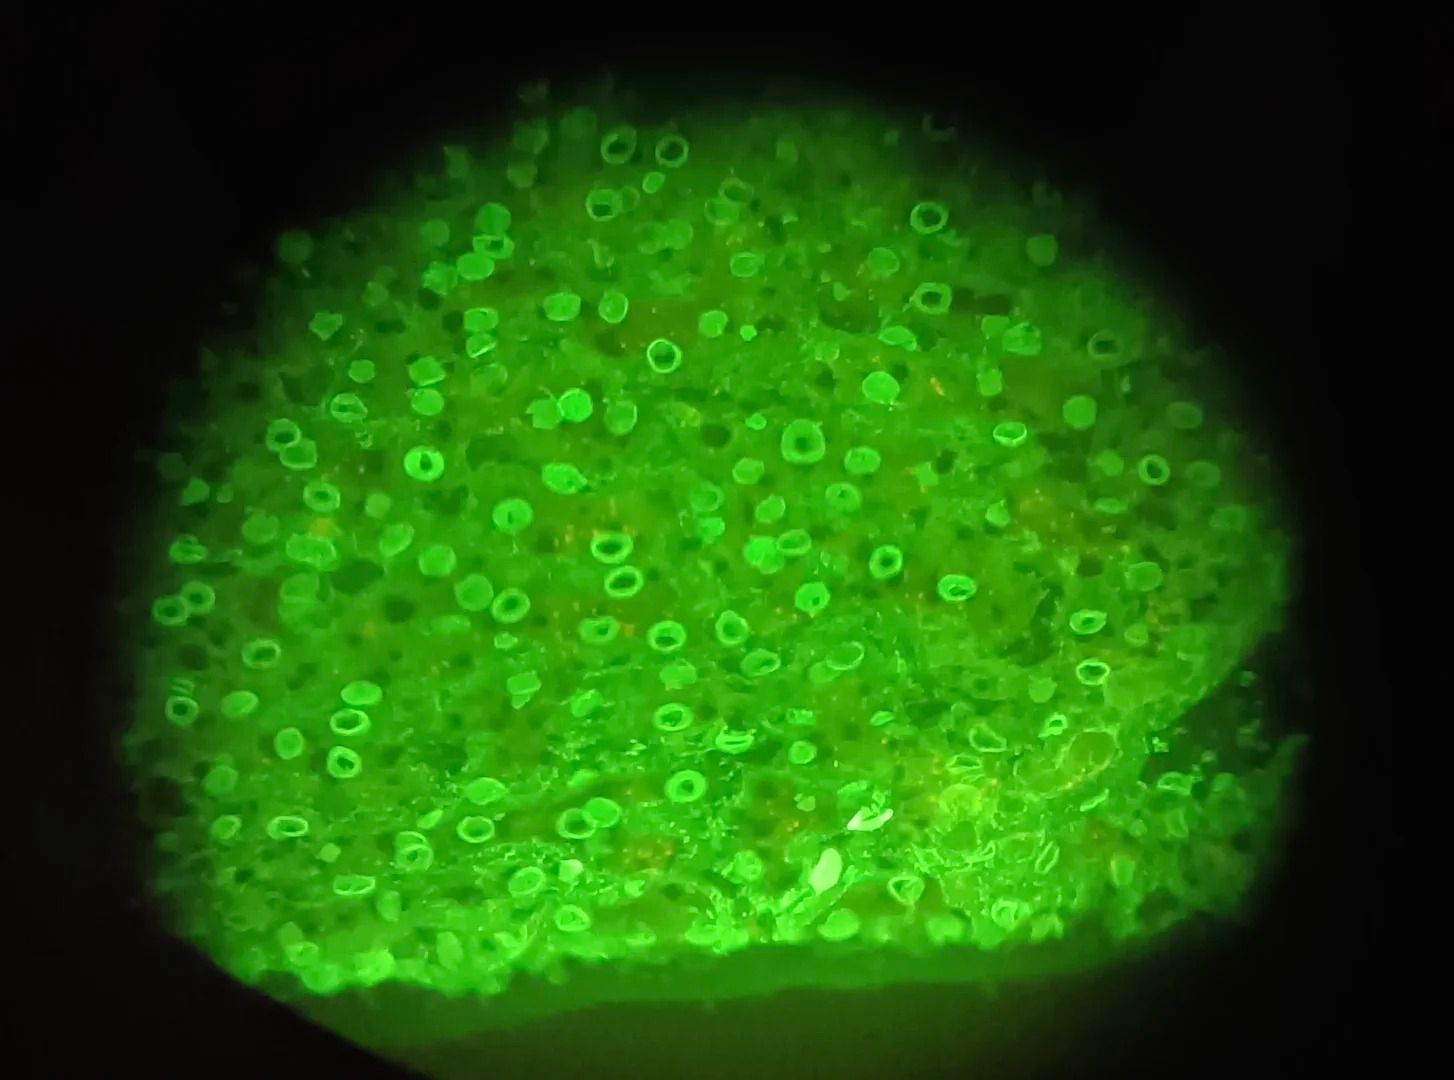

ANA核膜型

ANA著絲點型